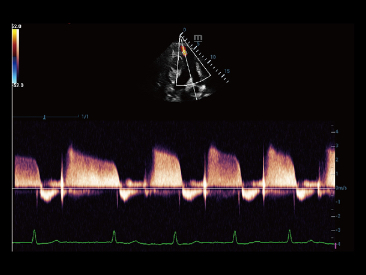

Neben der erstklassigen Bildqualit?t verbessert Resona 7 auch die klinischen Forschungsm?glichkeiten mit dem revolution?ren V Flow f├╝r die vaskul?re h?modynamische Bewertung und der intelligentesten Ebenenerfassung aus 3D-Datens?tzen f├╝r die f?tale ZNS-Diagnose. Mit der Kombination aus intuitiver, gestenbasierter Multi-Touch-Bedienung und allen wichtigen klinischen Funktionen ist das Resona 7 ein echter Wegbereiter f├╝r neue Ultraschall-Innovationen.

Die St?rken des Resona 7 sind bis ins kleinste Detail durchdacht. Seine erstklassige Bildqualit?t ist das Ergebnis einer erfolgreichen Fusion. Mindray und Zonare Medical Systems haben ihren Kernkompetenzen geb├╝ndelt, um ein Premiumsystem Wirklichkeit werden zu lassen. Dank der Vector Flow-Funktion k?nnen bei Gef??untersuchungen mehr als 400 Bilder pro Sekunde dargestellt werden. Somit entstehen ganz neue M?glichkeiten der Diagnose.